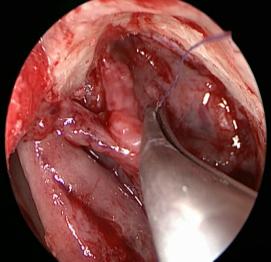

切開淚囊

縫合鼻腔與淚囊黏膜